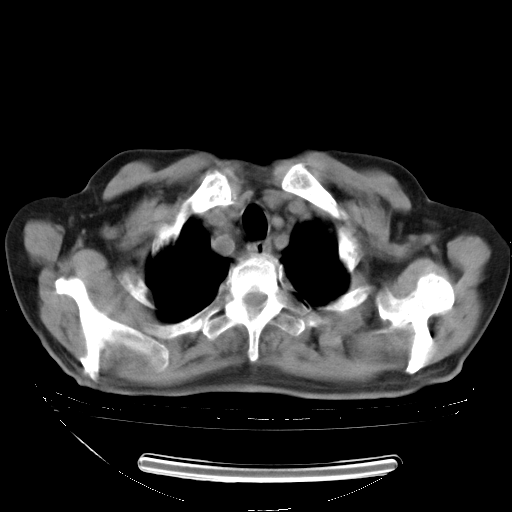

5月9日肺部CT(在4月27日齐鲁医院肺部CT描述部分肺组织磨玻璃样改变,12天后肺组织广泛磨玻璃样改变)

2009年5月9日肺部CT

大致读了系列胸部CT:纵隔窗无明显异常,肺窗:从4、27至今:主要是双肺中下野外带可见毛玻璃样改变,目前处于急性肺泡炎阶段,至于原因考虑1、结替组织或胶原血管性疾病所致?2、恶性疾病如恶组在肺部所致的表现或细支气管肺泡癌?3、药物或其它原因如肺蛋白沉着症所致肺泡炎目前不太可能?总之,明天就去请我院的呼吸科、感染科、血液科和临免专家会诊哈。